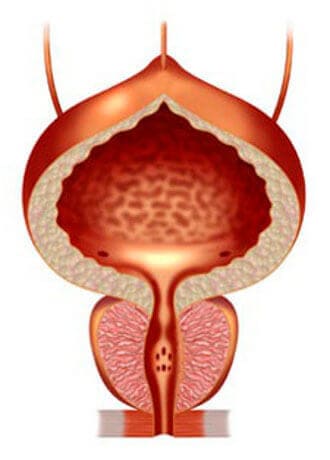

التهاب البروستاتا العادي

تضخم البروستاتا الحميد

إذا لم تعالج التهاب البروستاتا ، فإنه يتطور بسرعة كبيرة ويؤدي غالبا إلى ورم غدي في البروستاتا ("موت الذكورة")